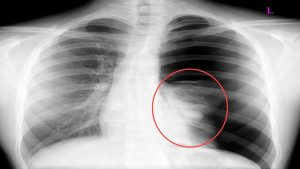

Giãn phế quản là một bệnh lý thuộc chuyên khoa hô hấp. Bệnh gây tổn thương trực tiếp đến phế quản, đường dẫn khí trong phổi, có thể dẫn tới nhiều biến chứng đáng lo ngại. Hãy cùng Docosan tìm hiểu về triệu chứng và các cách điều trị giãn phế quản trong y học […]